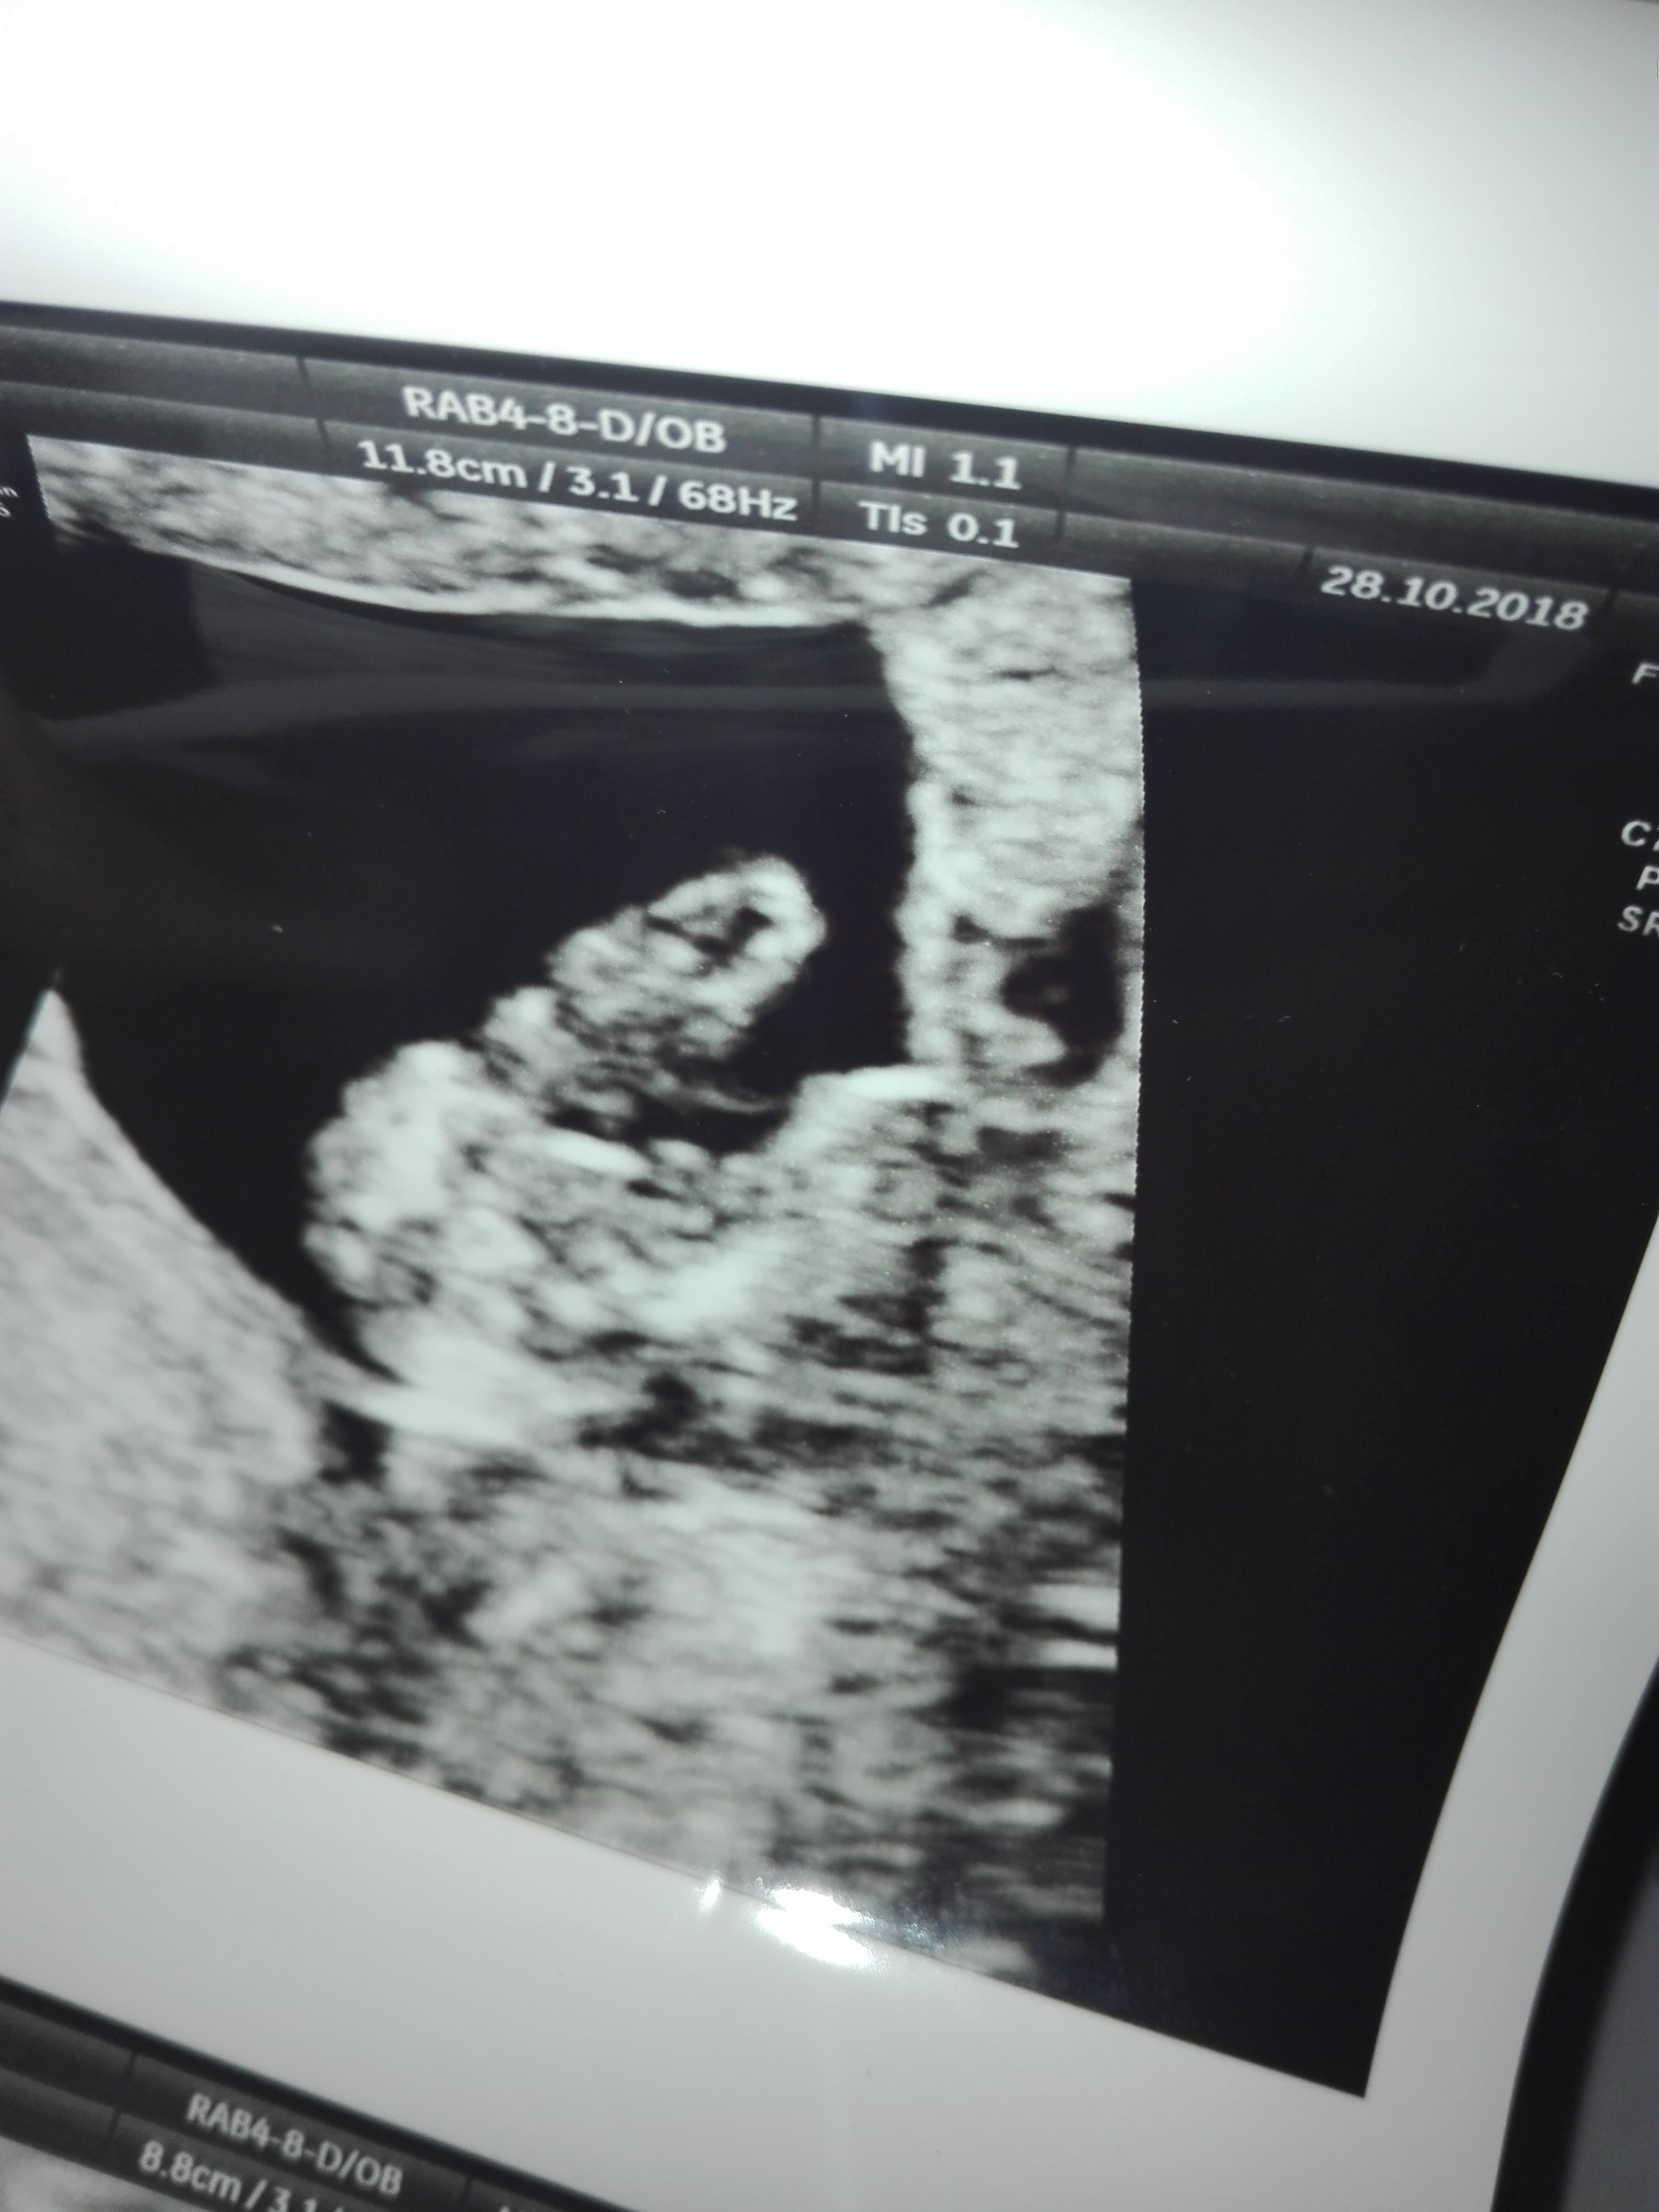

Witam w 19 tygodniu ciąży dowiedziałam się ze będę miała dziewczynkę w 20 tyg okazało się jednak , że to chłopak. Sama już nie wiem bo na jednym usg widać na pewno dziewuche a na drugim chłopca. Może to pempowina ?? Może ktoś mi pomoże rozwiązać ta zagadkę

mam takie zdjecie wydaje mi sie ze to ten siusiak tylko czy.on nie jest za.wysoko ? Z jakiej perspektywy jest to zdjecie ? Normalnie siusiak jest bardziej uniesiony niz lechtaczka ale on jest nie usniesiony tylko bardzo skierowany ku gorze o ile ja dobrze widze.I odbieram to zdjecie.